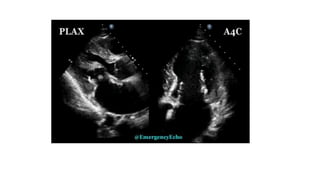

Large oscillating intracardiacmass suggestive of infective etiology